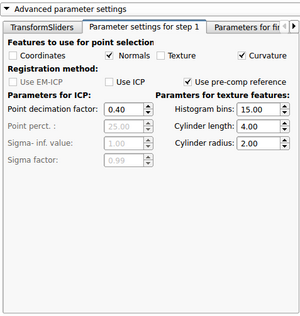

Tutorial and description of panelsUsing the first tab of the loadable module the user should provide the following input data: -3D CT image(volume) of non fractured bone (='Reference image') After providing the input data the 'Initialize reconstruction'-button should be pressed in order to create 3D models of the labelmaps and initialize the reconstruction process If the user wants to provide a better manual interaction the transform sliders (from within the fracture reconstruction) module can be used. Better initialization will decrease the calculation times for the subsequent alignment process and potentially lead to better results. The "Reset manual transform" button to reset the postion of each fragment to the state prior to the manual interaction. After the initialization process is finished the second tab will be opened. The 2D and 3D views will be updated and a surface rendering of the fragments and reference bone will be provided. The user can change colors, opacity and visibility for each single fragment.

After the first step of the reconstruction is finished and user can inspect the intermediate result. 2D and 3D views will be update according to the calculated transformations. At this point the user, the following scenarios are possible: 1) Good registration - Accept registration without performing further registration (fine tuning part will be skipped). By pressing the "Start fine tuning" button the second part of the reconstruction process in which the fragments will be aligned against each other (without using the reference bone) will be started. The parameters for this step can be changed in the corresponding parameter tab ("Parameters for fine tuning") After the calculations for the fine tuning step are finished, the last tab will be opened ("Result step 2"). Again 2D and 3D views will be updated accordingly and the same 4 scenarios as in the previous step are possible.  Updated 2D and 3D views after final step of reconstruction. Note that the visible gaps are due to missing bone that has been "simulated" in this (toy) example. This view was generated using a wireframe representatioin of the fragments in combination with a volume rendering of CT dataset of the (healthy) reference bone